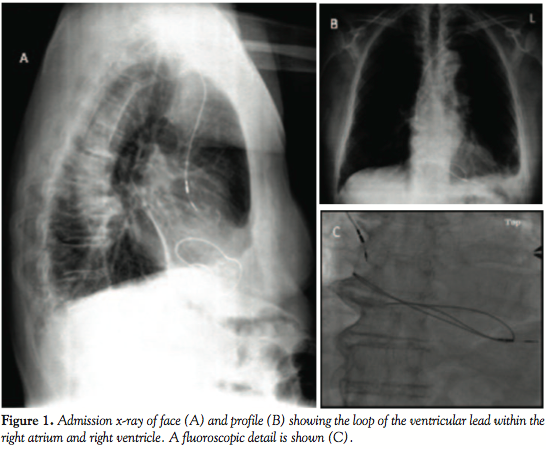

Case Report. An 83-year-old hypertensive man who had undergone implantation of a dual-chamber pacemaker due to symptomatic sinus bradycardia presented with local inflammation in the generator pocket 2 years after the implantation. At presentation the patient was asymptomatic, afebrile and had no signs of systemic infection. The C-reactive protein levels, the erythrocyte sedimentation rate, and the white blood cell count were normal and blood cultures were negative. Partial removal of the device was decided at the first referral center. Debridement of the infected area was performed, the generator and the proximal part of the leads were removed, and the remaining leads were severed from the infected area and abandoned. Cultures of the debrided tissue revealed Staphylococcus epidermidis infection, and the patient was treated with 15 days of intravenous antistaphylococcal antibiotics and subsequent oral therapy. The patient at presentation was in sinus rhythm, was non-pacemaker dependent, and was not receiving anticoagulants. Twenty-five days after the device extraction and with good healing of the wound, the patient had a transient ischemic attack (TIA). The patient was therefore referred to our cardiology department, where an emergency thoracotomy was performed for further evaluation and fluoroscopic lead extraction. The chest x-ray performed at admission (Figures 1A and 1B) showed that the distal part of the right ventricular lead had been dislodged and formed a loop within the right atrium and right ventricle and that the atrial lead had “fallen” out of the appendage. A detailed view of the loop based on the fluoroscopic study is shown in Figure 1C.